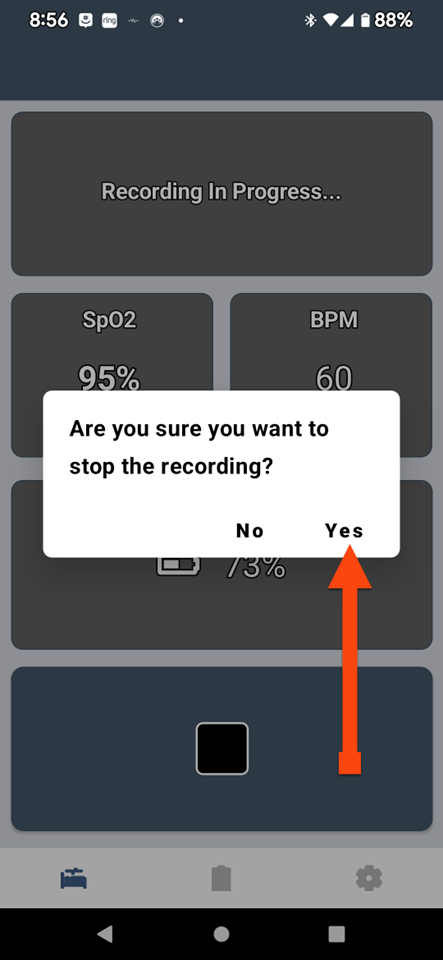

SLEEPIMAGE APP (Android)

SLEEPIMAGE APP (Android)

SLEEPIMAGE APP (Android)

SLEEPIMAGE APP (Android)

SLEEPIMAGE APP (Android)

SLEEPIMAGE APP (Android)

SLEEPIMAGE APP (Android)

SLEEPIMAGE APP (Android)

SLEEPIMAGE APP (Android)

SLEEPIMAGE APP (Android)

SLEEPIMAGE APP (Android)

SLEEPIMAGE APP (Android)

SLEEPIMAGE APP (Android)

SLEEPIMAGE APP (Android)

SLEEPIMAGE APP (Android)

SLEEPIMAGE APP (Android)

SLEEPIMAGE APP (Android)

SLEEPIMAGE APP (Android)

SLEEPIMAGE APP (Android)

SLEEPIMAGE APP (Android)

SLEEPIMAGE APP (Android)

SLEEPIMAGE APP (Android)

SLEEPIMAGE APP (Android)

SLEEPIMAGE APP (Android)

SLEEPIMAGE APP (Android)

SLEEPIMAGE APP (Android)

SLEEPIMAGE APP (Android)

SLEEPIMAGE APP (Android)

SLEEPIMAGE APP (Android)